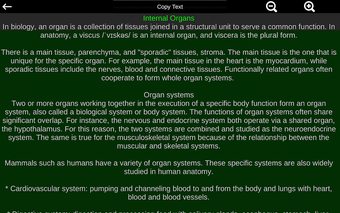

Diese Anwendung zeigt ein dreidimensionales Modell der menschlichen Körperorgane und eine Beschreibung aller von ihnen.

Die Anwendung soll das Studium der Anatomie in Medizin, Biologie oder anderen Fächern ergänzen.

Sie können die App verwenden, um herauszufinden, welches die verschiedenen Körperorgane sind und welche Funktionen sie haben.